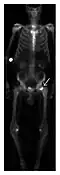

Proximal femoral fractures usually occur in osteoporotic patients, and their signs include subtle neck angulation, trabecular angulation, and subcapital impaction line. A frog-leg lateral view may be helpful if the greater trochanter is short enough. However, positioning can be difficult because of hip pain. In patients with strong suspicion of proximal femoral fracture and negative radiographs, MRI limited to coronal T1 W images and scintigraphy can be highly valuable (Figures 13 and 14). Such an option, with limited examination time, is cost-effective and allows reliable exclusion or confirmation of the diagnosis, preventing an unnecessary stay at the hospital or delayed treatment. Moreover, MRI helps to detect soft tissue abnormalities which are more frequently seen in femoral, acetabular, and pubic injuries than sacral lesions. Concomitant fractures are also frequently seen in typical pelvic sites.[1]

-

a -

b

Figure 14: Subcapital insufficiency fracture in a 55-year-old man with a left hip pain without a history of trauma. Anteroposterior and Lauenstein view radiographs centered on the left hip do not show an obvious fracture line, but mild acetabular osteophytosis was noted consistent with hip osteoarthritis (not shown). (a) Coronal T1-weighted MRI shows a linear low-signal band through the femoral neck corresponding to a fracture line (arrowheads). (b) Bone scintigraphy shows focal uptake (arrow) corresponding to the fracture.[1]